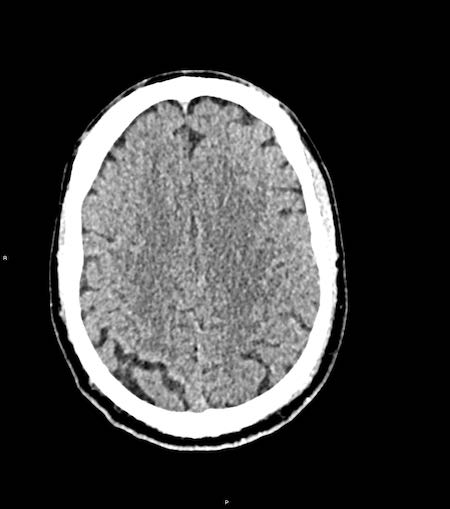

Tụ máu dưới màng cứng đồng tỷ trọng

Khi tụ máu dưới màng cứng tiến triển theo thời gian, tỷ trọng của khối tụ máu sẽ giảm dần và có thể tương đương với tỷ trọng của nhu mô não, khiến việc phát hiện tổn thương trở nên khó khăn.

Đây là trường hợp tụ máu dưới màng cứng đồng tỷ trọng rất khó phát hiện (các mũi tên).

Lưu ý rằng ở mức cắt cao hơn có tụ máu dưới màng cứng hai bên.